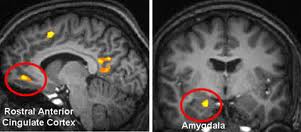

A rede de modo padrão geralmente está associada ao processamento de informações relacionadas. Em precuneus, que é também responsável por processos introspectivos[1, 9], ocorre um aumento da atividade em transes com sugestões de paralisia. Este é também o caso com sugestões específicas para o alívio da dor. Curiosamente, não há nenhuma reação com transe passivo. Isto está alinhado com o conceito de dissociação de Hilgard. Além disso, ocorre também algumas mudanças no córtex cingulado anterior (ACC) e no córtex orbitofrontal.